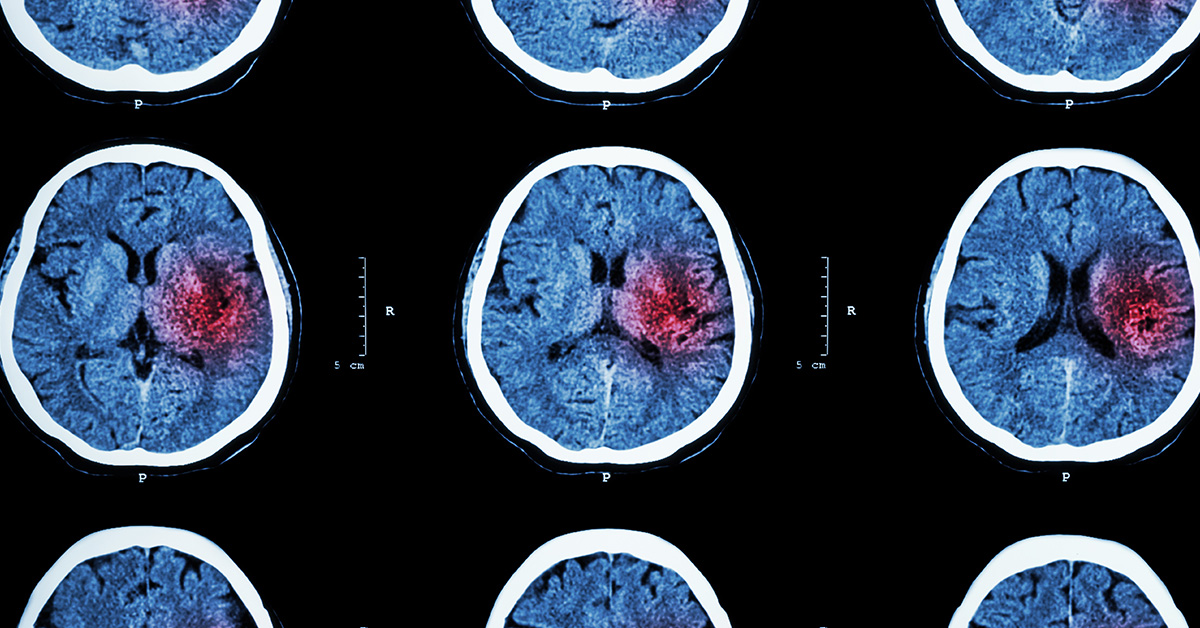

Within two days of arriving in the hospital, Pam had a stroke – a complication that a small percentage of people infected with COVID-19 experience.

Strokes happen when the brain’s blood supply is cut off, such as when a blood clot or blockage occurs (ischemic stroke) or an artery in the brain ruptures (hemorrhagic stroke). Ischemic strokes are much more common than hemorrhagic, and this is the type of stroke Pam experienced.